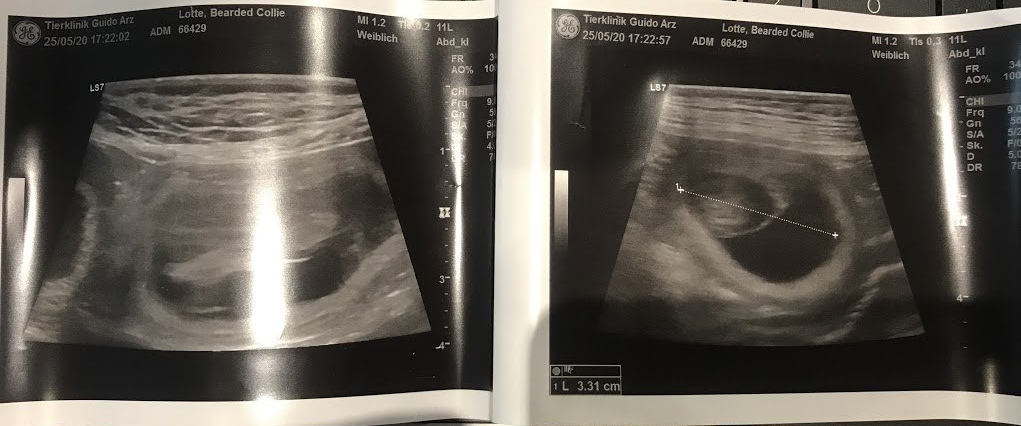

乐天怀孕了……我们怀疑很久了。她没有吃东西,感到恶心……实际上所有迹象都适用于她。

我们的兽医为我们感到高兴……我对她和克鲁尼说不超过 5 只小狗,但他们不听我的……根据兽医的说法,她“吃饱了”🤦♀️。

我希望没有太多。